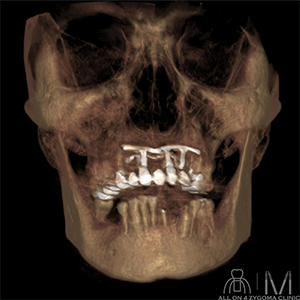

術前CT画像所見

上顎前歯相当部にはブレードインプラントを認める。インプラント周囲に炎症を示唆する明らかな所見は認めない。下顎骨は骨硬化を認める。 両側頬骨の骨幅は十分な幅を認める。 両側上顎洞に明らかな病変は認めない。